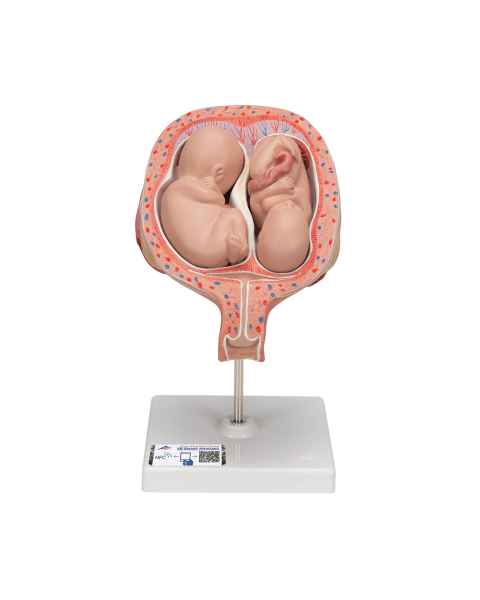

Female anatomical models are an ideal teaching aid to help educate both students and patients. Our extensive selection of female anatomy models includes female pelvic models, pregnancy series models, pelvis skeleton models, delivery/childbirth simulators, clinical breast trainers and self-exam models, uterus/ovary models, and more. Teaching simulators and self-exam models are excellent for educating students and patient education.

For example, the Wearable Breast Self-Exam Model can be easily worn, in order to better train and practice breast self-examination. Our line of prevention and detection models includes the Realistic Left Breast Model, Uterus/Ovary Model with Pathologies, Model of the Female Breast, and the Clinical Breast Trainer. Obstetricians will benefit from owning female anatomy figures of uteri and pelvises with fetuses inside, as well as sets of models that demonstrate the stages of fertilization. Women, particularly first-time mothers, will appreciate having a female education model that clearly illustrates the pregnancy process and what exactly is occurring inside of their body.